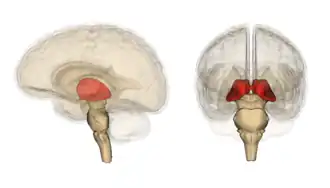

Le thalamus (du grec θάλαμος / thálamos, « chambre, maison ») est une structure anatomique paire de substance grise cérébrale diencéphalique. Les deux thalamus sont situés de part et d'autre du IIIe ventricule dont ils constituent les parois latérales. Situé en position intermédiaire entre cortex et tronc cérébral, le thalamus a principalement une fonction de relais et d'intégration des afférences sensitives et sensorielles et des efférences motrices, ainsi que de régulation de la conscience, de la vigilance et du sommeil.

Les deux noyaux thalamiques se présentent comme deux masses ovoïdes de substance grise, obliques en avant et en dedans selon un axe d'environ 60°, à grosse extrémité postérieure (pulvinar) et essentiellement en rapport avec :